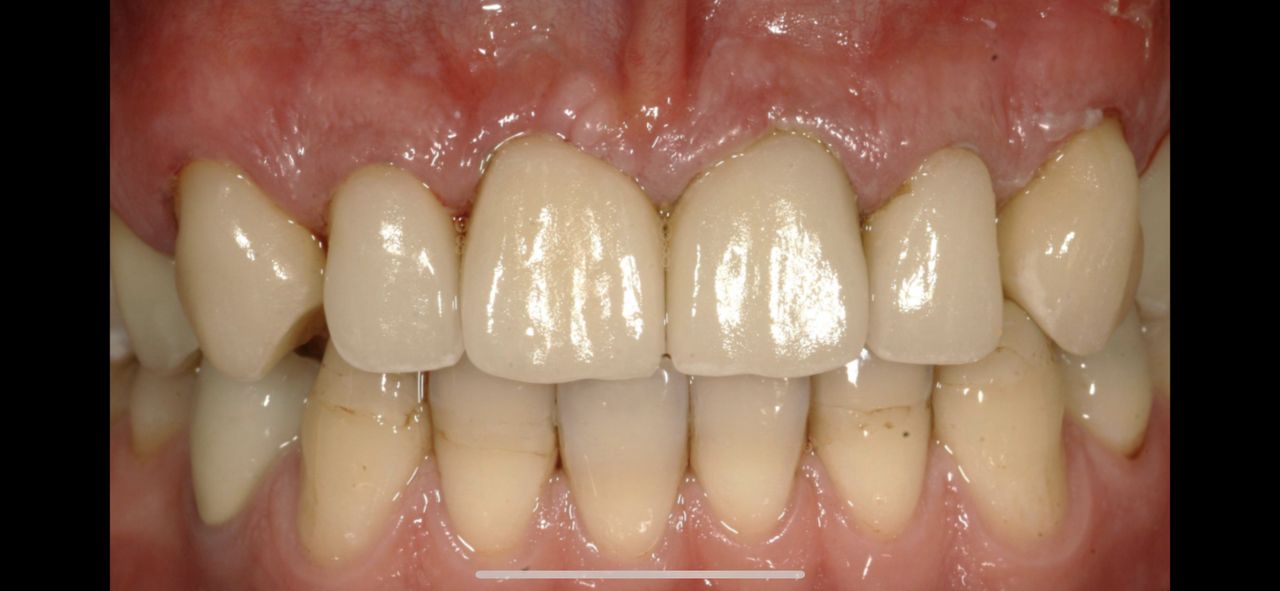

Z pełnym przekonaniem polecam leczenie protetyczne w tym gabinecie. Wykonane korony porcelanowo-cyrkonowe spełniły moje oczekiwania zarówno pod względem estetycznym, jak i funkcjonalnym. Efekt końcowy jest bardzo naturalny, korony są idealnie dopasowane i komfortowe w codziennym użytkowaniu. Cały proces leczenia przebiegał sprawnie, z dokładnym omówieniem planu oraz poszczególnych etapów. Lekarz wykazał się dużą wiedzą, precyzją i dbałością o detale, co w protetyce ma kluczowe znaczenie. Dodatkowo czułem się zaopiekowany i spokojny, co zdecydowanie podnosi komfort leczenia.

• Duo-Dent korony cyrkonowe  •

• D

Pan dok.Polakowski to profesjonalista, tam gdzie nikt nie chciał zająć się moimi zębami

P.dok wyczarowal piękny uśmiech.

Dziękuję, i z czystym sumieniem mogę polecić każdemu kto ma problemy z zębami.

• Duo-Dent odbudowa zębów  •